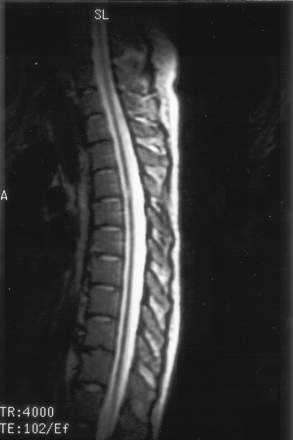

On the dermatologic examination, diffuse asymptomatic papules were found, mostly in the lower limbs. These lesions had a diameter of a few millimeters, were surrounded by a erythematous rim, and their color was pink, with a central atrophic area characterized by adherent whitish desquamation (Fig 1); a skin biopsy on the leg confirmed the diagnosis of Degos disease (Fig 2). The neurologic examination noted anisocoria, hearing loss on the left side, diffuse muscle hypotrophy, impaired finger movements, mild paresis of the right arm, paralysis of both legs, symmetrically reduced muscular reflexes, hypoesthesia, hypopallesthesia of the lower limbs, constipation, and urinary incontinence. No fever or meningeal signs were present. Brain MR imaging (Figs 3–5) showed both old and new ischemic lesions, mainly present in the left hemisphere, and numerous small nodules, localized in both the cerebral and the cerebellar cortices. A diffuse and homogeneous thickening of the meninges, with some subdural fluid accumulation, was also evident in the frontoparietal region. Ependymal enhancement was noted in the atrium of the right lateral ventricle. Hydrocephalus and venous thromboses were ruled out. Spinal MR imaging showed thinning of the spinal cord, with mild alteration of the signal intensity in the thoracic cord (Fig 6). A subtle, focal cord enhancement was found in the cervical and thoracic cord (Fig 7).

T2 sagittal image shows diffuse spinal cord thinning and midthoracic focal hyperintensity.